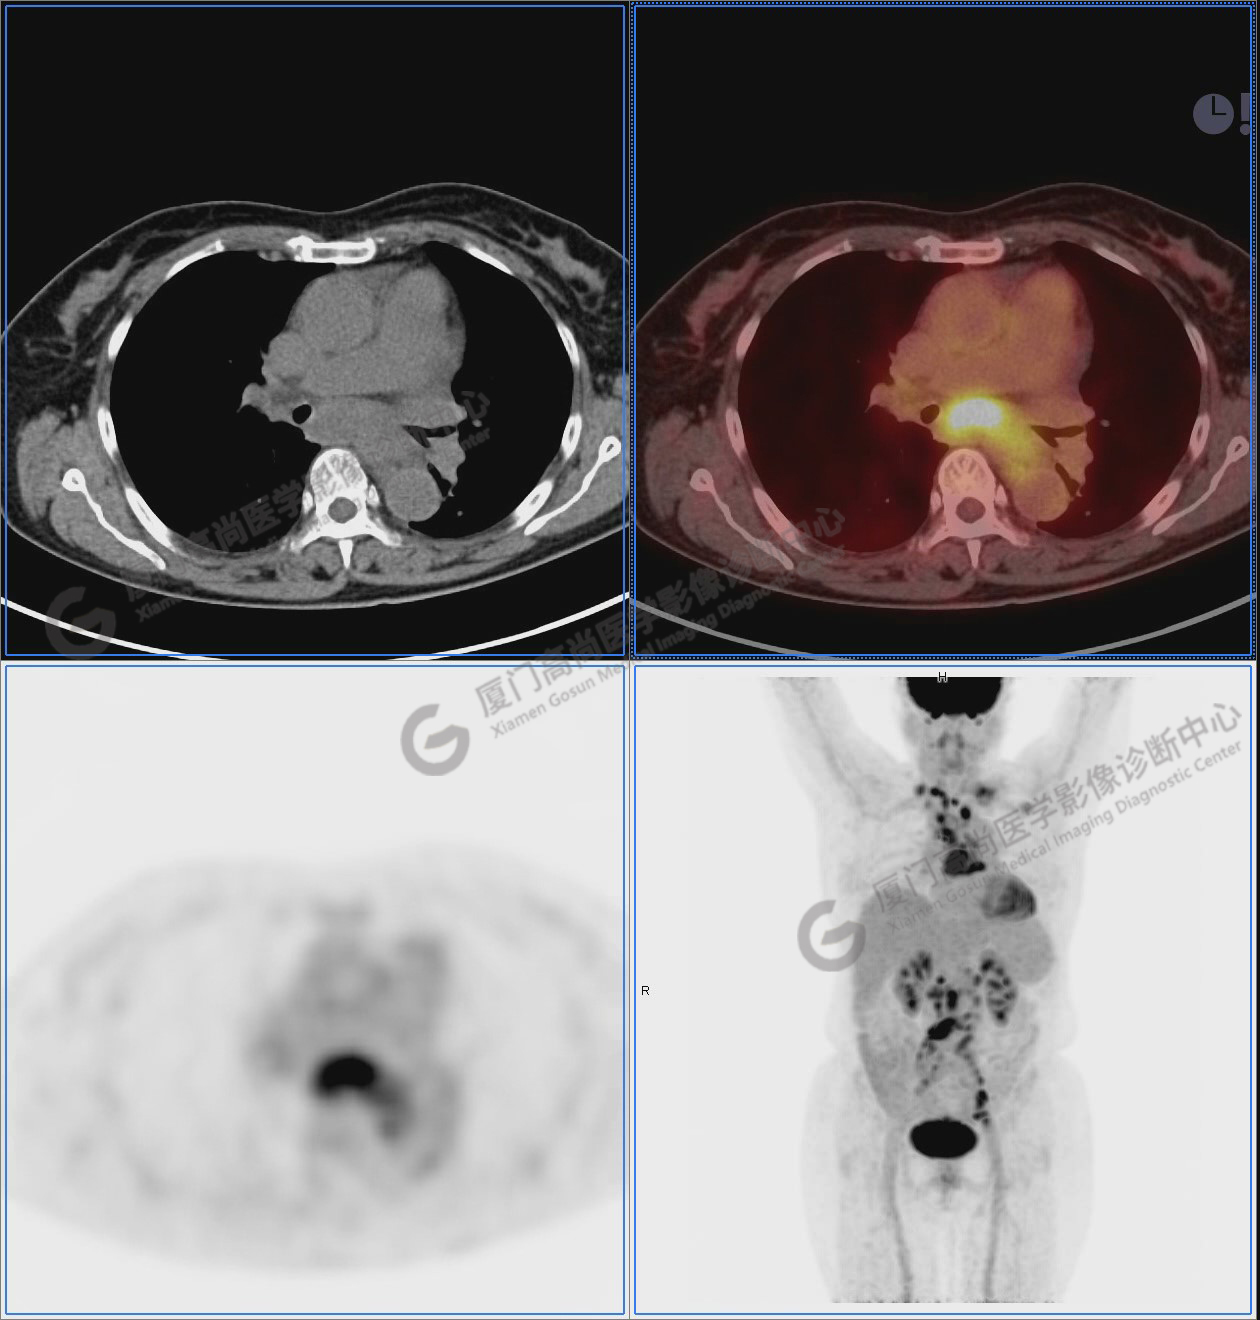

圖2-9:雙側(cè)鎖骨區(qū)、縱隔、右側(cè)內(nèi)乳區(qū)、腸系膜緣、腹膜后、雙側(cè)髂血管旁及盆腔多發(fā)腫大淋巴結(jié)影,代謝不同程度增高,考慮為轉(zhuǎn)移。

圖6

圖7

圖8

圖9

圖10-11:子宮頸軟組織腫塊,代謝異常增高,考慮為宮頸癌。